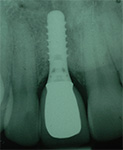

Qu’est-ce qu’un implant dentaire ?

C’est une racine artificielle.

Cette racine artificielle permet de fixer une nouvelle couronne restaurant une nouvelle dent. Plusieurs implants peuvent porter plusieurs dents ou un bridge, jusqu’à la restauration d’une arcade complète. Les implants permettent également de stabiliser une prothèse amovible.

L‘ostéointégration est une connexion directe, structurelle et fonctionnelle entre un os vivant et la surface d‘un implant portant une charge.